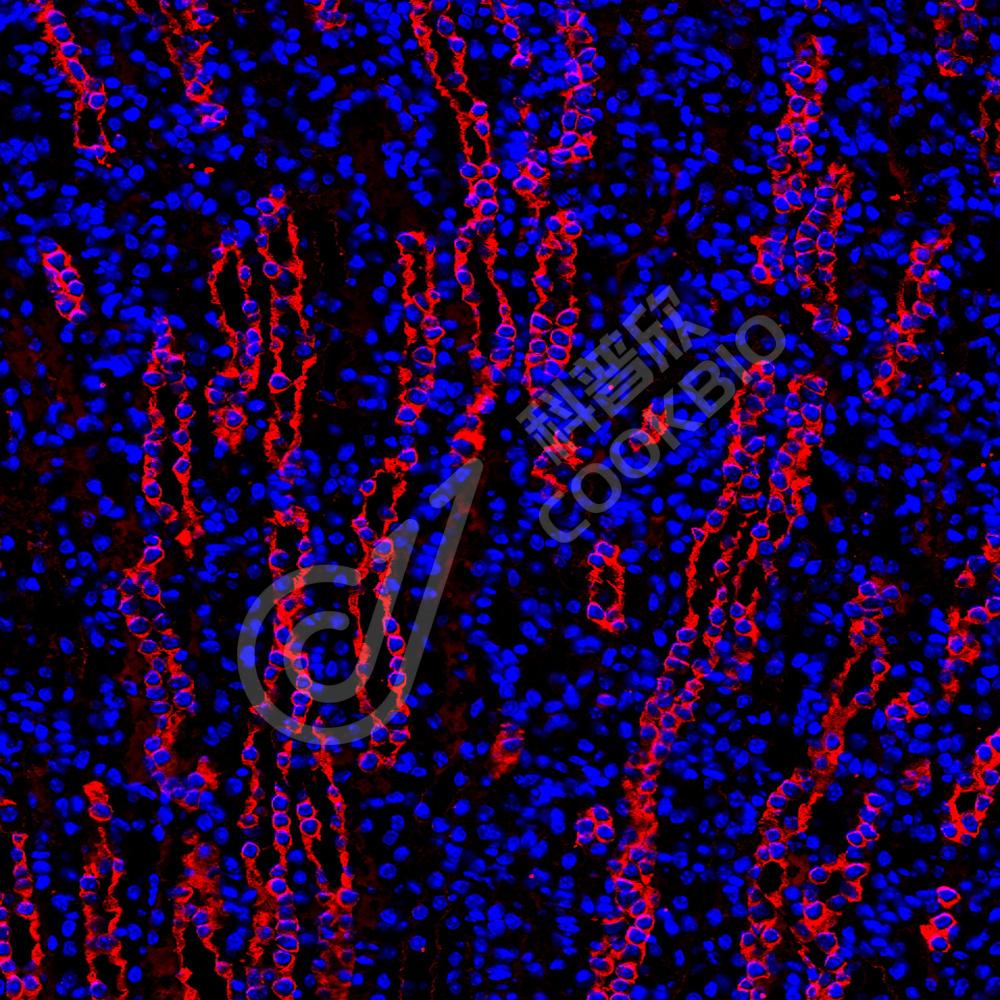

IF检测non-muscle Myosin IIB/MYH10蛋白(货号 K2363561)(红色).

样品: 人乳腺癌, 4%多聚甲醛 (货号KSG1101) 固定12-24小时.

抗原修复: 柠檬酸抗原修复液(干粉, pH 6.0) (KSG1201), 高压锅均匀喷气计时2分钟.

封闭: 3% BSA(货号KSGC305010)的PBS溶液, 室温孵育30分钟.

—抗: 1: 2300稀释, 4℃ 孵育过夜.

二抗: Cy3标记山羊抗小鼠IgG (H+L) (货号KB63903), 1: 300稀释, 室温孵育1小时.